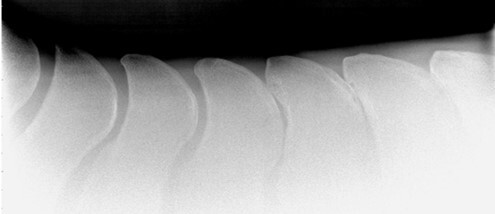

Q

What disease is this?

A

Dorsal spinous process impingement/’kissing spines’